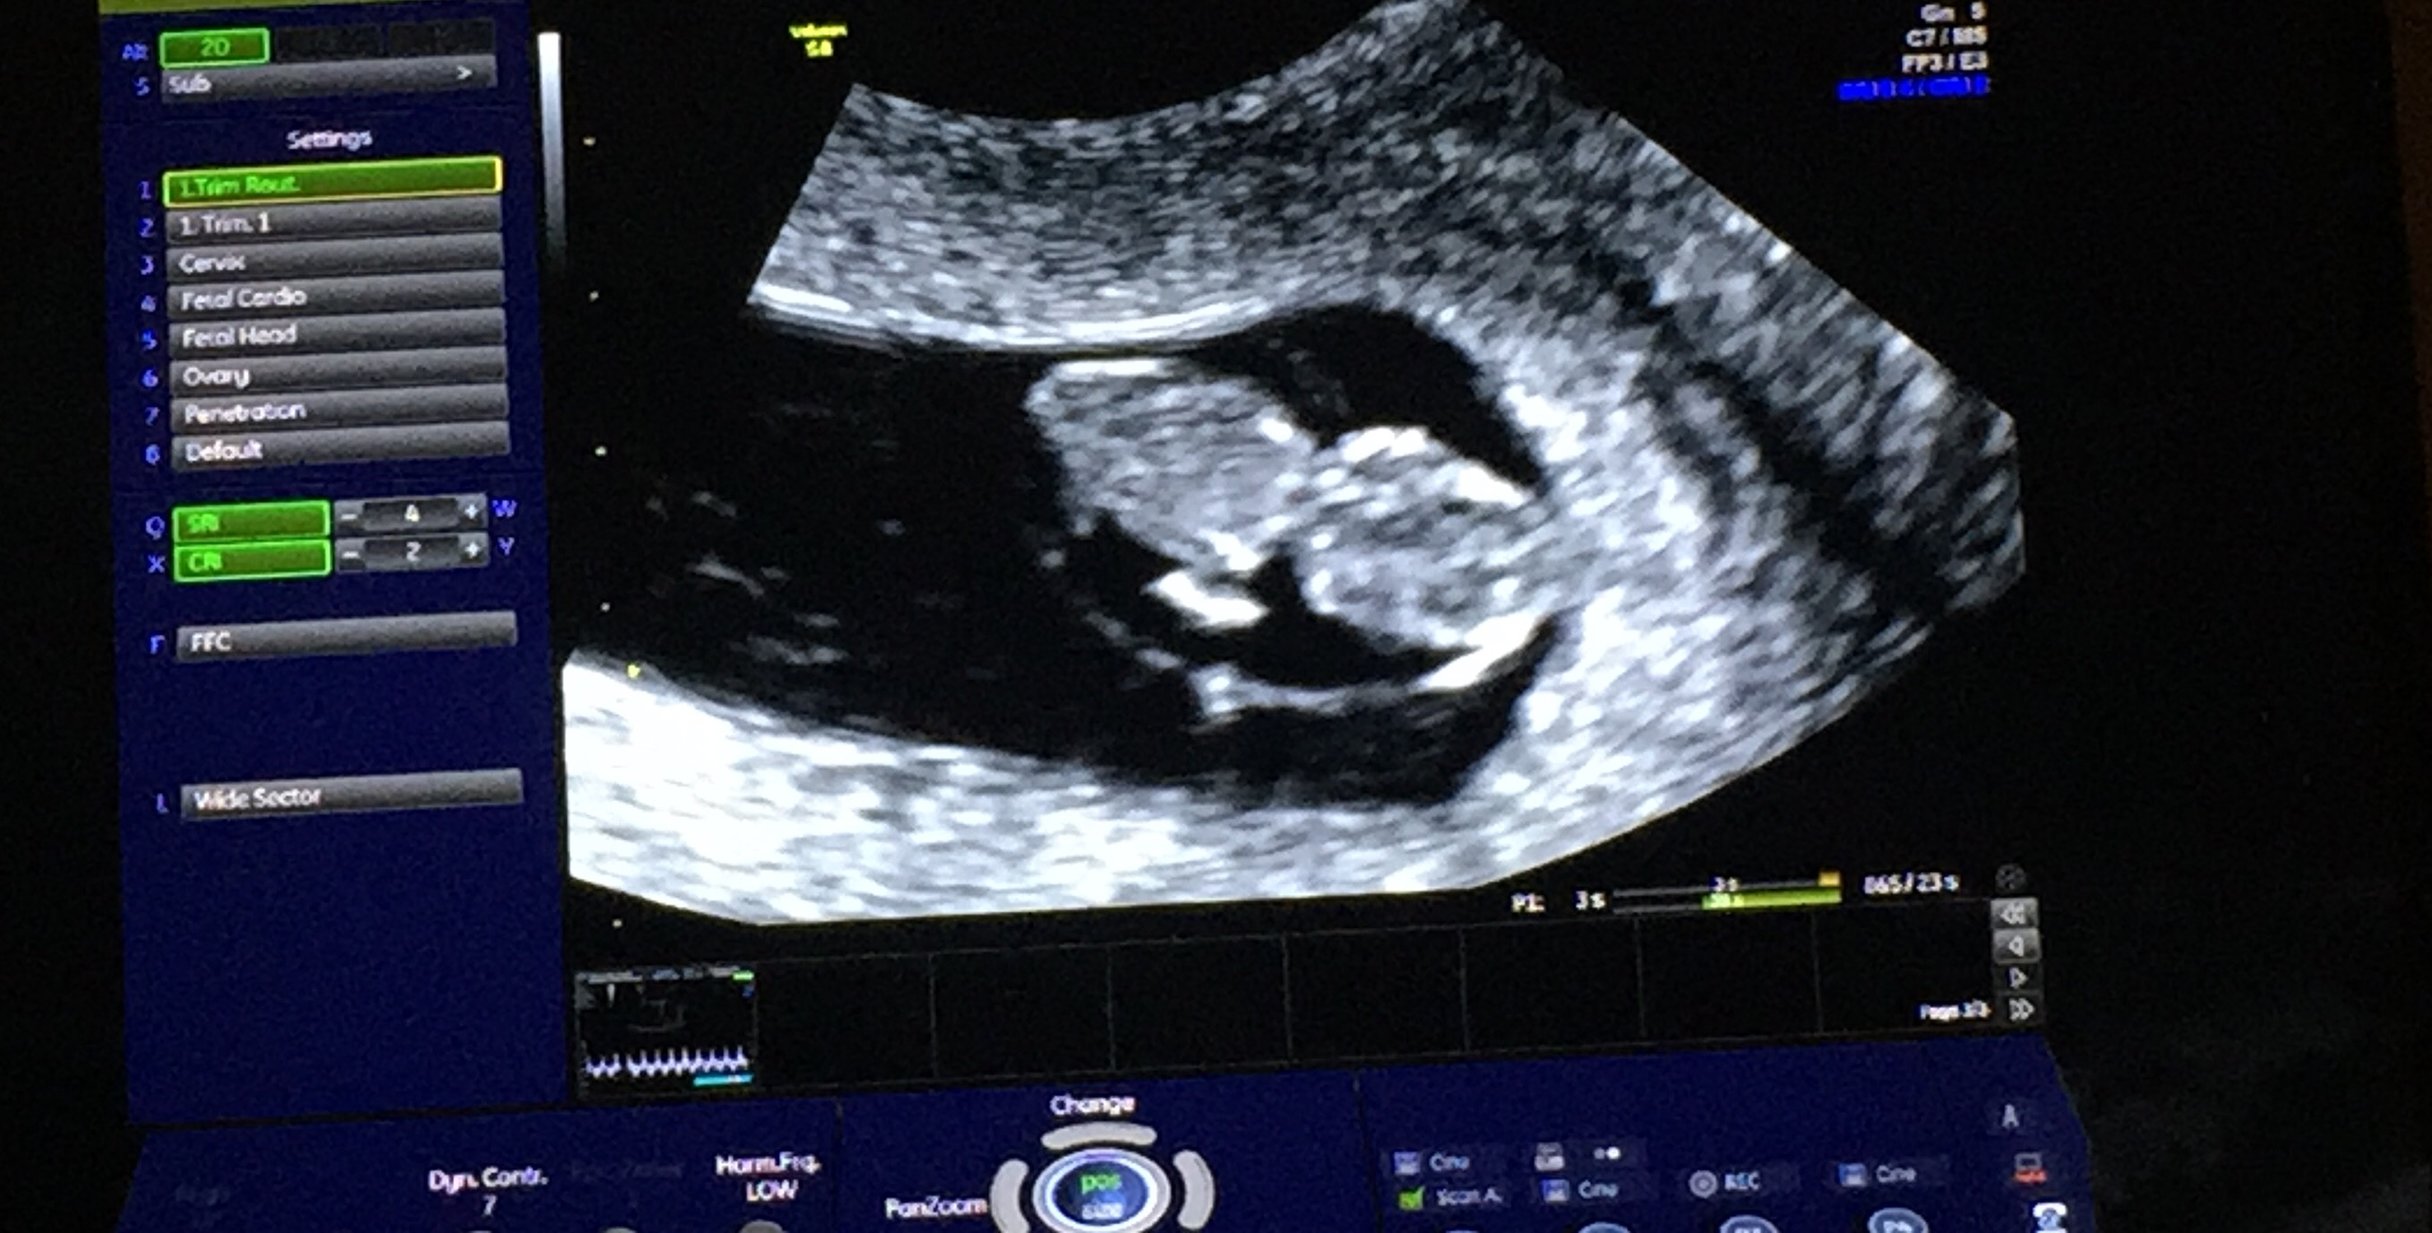

Here is our little bean, measuring 6+1 today. EDD is 3/28. Heart rate was in the mid-90's so we have a follow up ultrasound in two weeks!